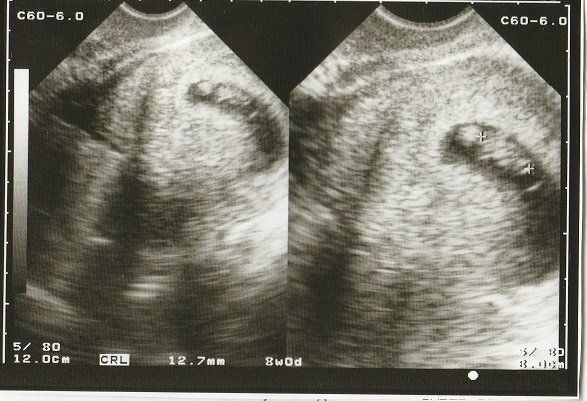

ちゃじゅびさんの妊娠8週目のエコー写真 10mm以上に成長

CRL(頭殿長=頭からおしりまでの長さ)が10mmを超えました。

順調に大きくなっていますが、まだまだ「大丈夫だろうか?」という不安が大きかった時期。